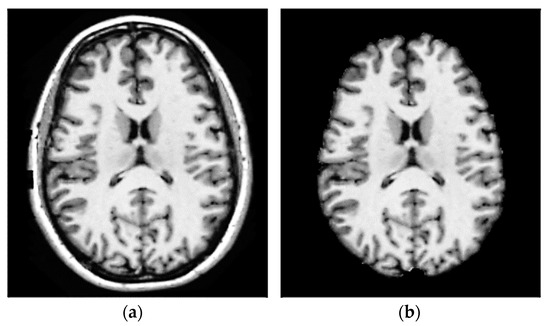

3.1. Step 1 Preprocessing Phase